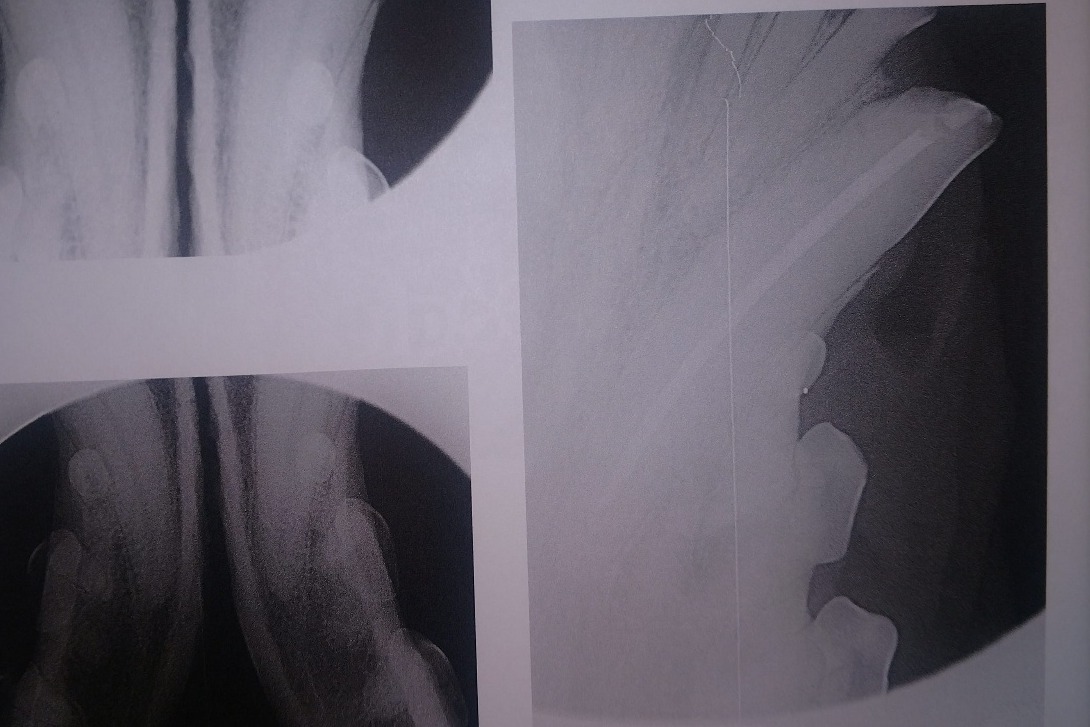

The following photos are her radiographs for anyone that knows how to read them, so you can see all the dead teeth that need future extractions, and some show the root canals:

The radiographs laid out a dim story of that long term damage: all 4 canine teeth were dead, 2 of those canines were broken off from the recent attempt on the gate; all of her lower incisors, and several molars on each side were also dead. The vet was surprised, in spite of massively evident wear and tear, that her upper incisors appeared to still be alive. More of her teeth were dead than live. However, there was some good news in that her gums were completely free of gum disease, she had very little plaque and tartar buildup, and that she hadn't lost any of the bone her teeth were seated in.

So I chose the slightly worse broken canine (bottom left) and it's upper companion to get root canals that day. The upper right broken canine, in the photo above, would be much easier for me to see to monitor its condition while we saved up for more surgeries. That surgery, including the consultation, radiographs, and blood tests, came out to a total of $2,867.82.